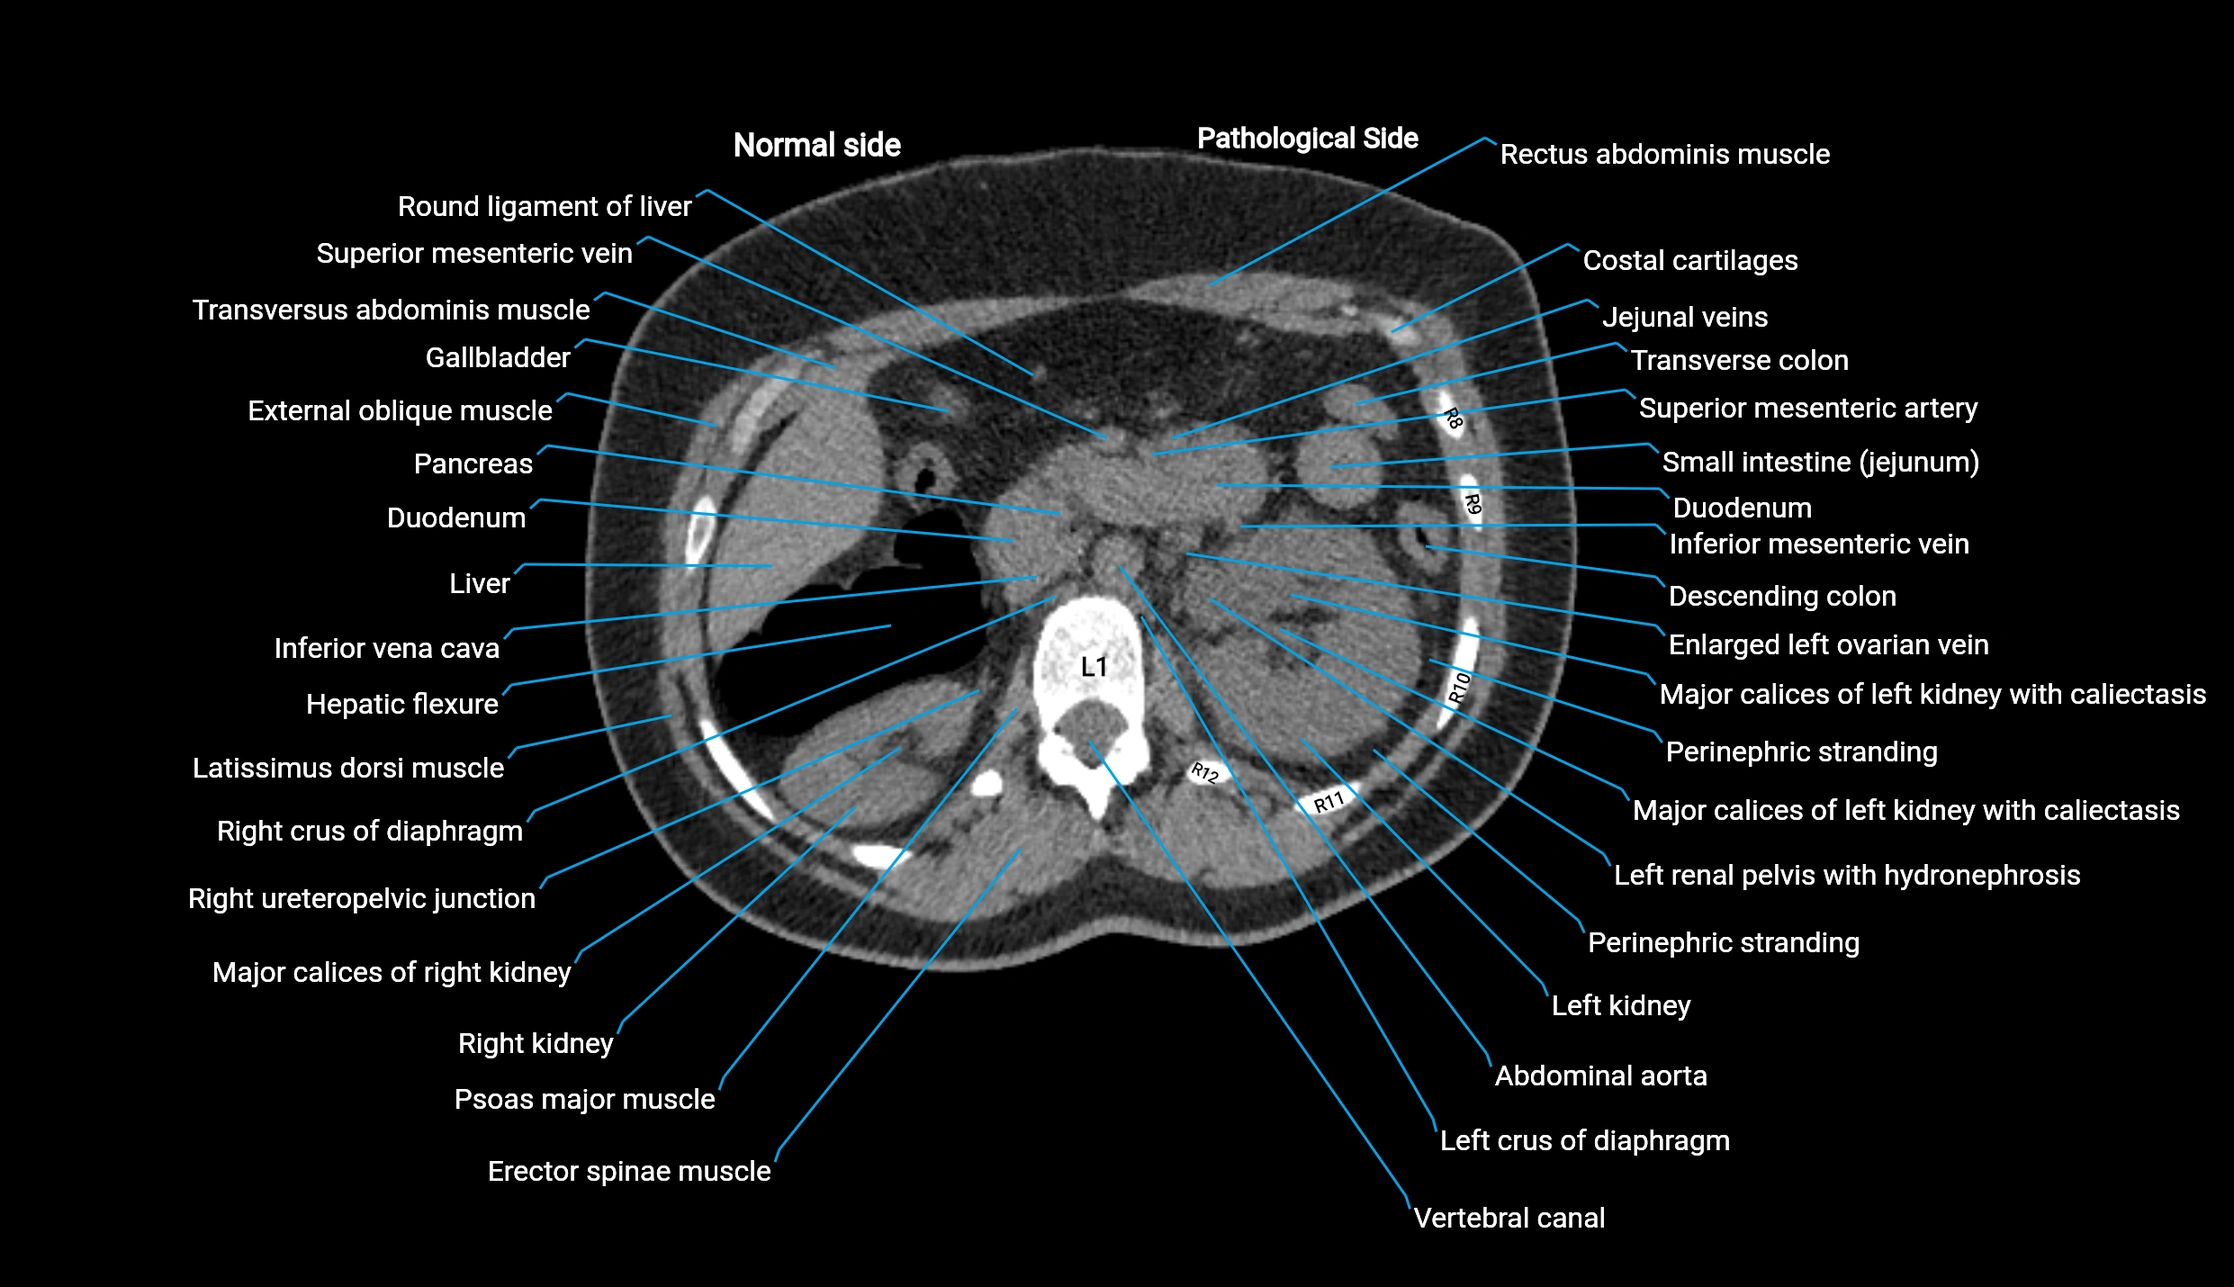

CT Appearance

Post-Contrast CT (Contrast-Enhanced CT):

• Portal venous phase:

• Anterior right portal branch enhances intensely and homogeneously

• Clearly separates from posterior branch

• Branching pattern to segments V and VIII sharply defined

• Arterial phase:

• Slight enhancement but less conspicuous than in portal phase

• Coronal and sagittal reconstructions:

• Optimal visualization of segmental bifurcation

• Used for preoperative liver mapping

• CT liver segmentation:

• RAPV acts as the principal boundary landmark for dividing anterior vs. posterior right hepatic segments